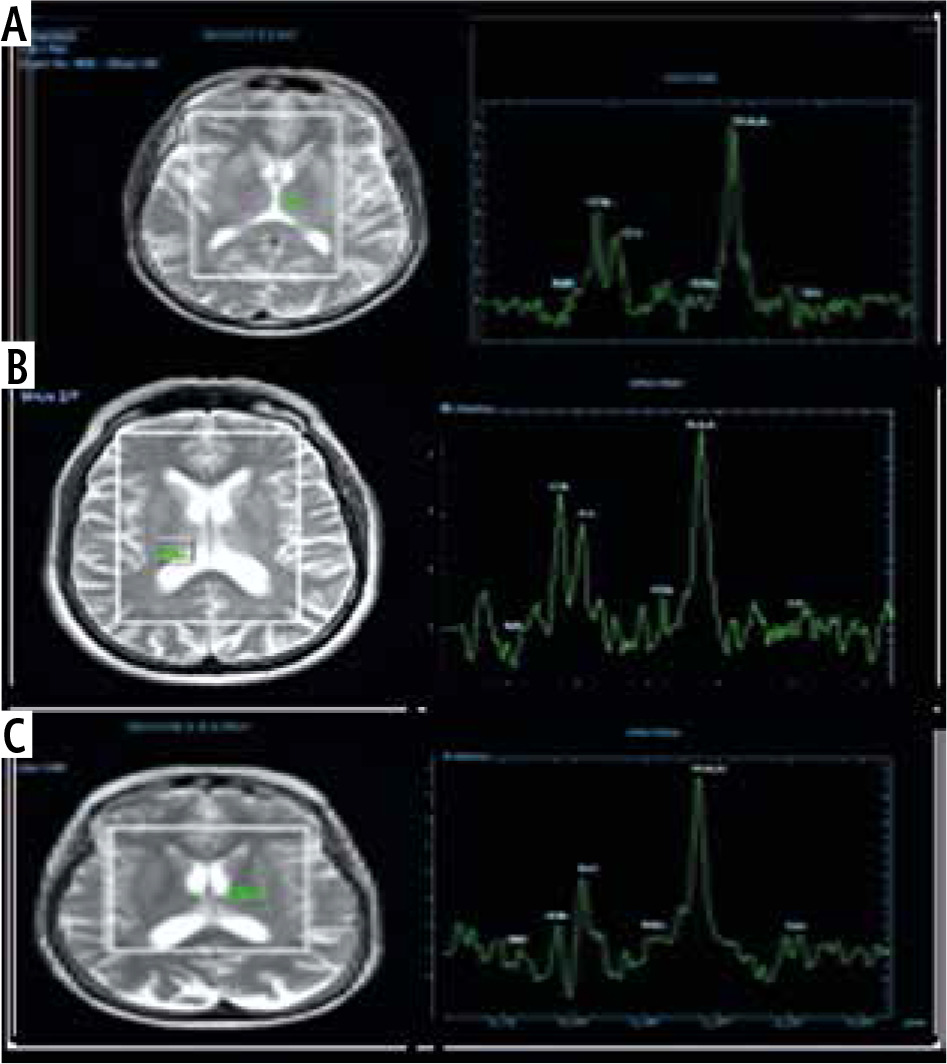

The MRS characteristics in the basal ganglia or thalamus demonstrated an increase in the brain metabolite Glx with a significant correlation to the presence and grade of HE, as we found its presence with low amounts in the control group, whereas in overt HE, we found large amounts of Glx in the brain with a significant difference (p = 0.001). Other brain metabolites, such as Cho and mI, were present in large quantities in the control group, as shown in Figure 1, which displayed a normal MRS evaluation spectrum. However, in the overt HE groups, we observed a significant decline in their quantities (p = 0.001). Two brain metabolites (NAA and Cr) were not significantly different between all grades of HE and the control groups (p = 0.47 and 0.38, respectively) (Table 3, Fig. 2).

Fig. 2

Magnetic resonance spectroscopy (MRS) in: A) a healthy patient, B) a cirrhotic patient with minimal hepatic encephalopathy (MHE), and C) a cirrhotic patient with overt HE showing increase of glutamate/glutamine complex (Glx) in cirrhotic patient with MHE and marked increase of Glx in cirrhotic patients with overt HE, decrease of myoinositol and choline values in cirrhotic patient with MHE and marked decrease in cirrhotic patient with overt HE. The region of interest (ROI) was located in the thalamus on MRS

In cirrhotic patients with MHE and over HE, the ratios of integrals of various metabolites were calculated and revealed that Glx/Cr was significantly increased, whereas mI/Cr and Cho/Cr were significantly decreased. There was no significant difference in NAA/Cr ratio (Table 4).

1H-MRS is used to assess diffuse brain metabolic disorders [17]. 1H-MRS is based on the evaluation of proton relaxation in a small volume of tissue to obtain a spectrum of signals dependent on frequency, with each metabolite occupying a specific position along the spectrum [18].

The alterations of brain metabolites in cirrhotic patients were tracked using 1H-MRS. Studies using proton spectroscopy revealed an increase in glutamine and glutamate peaks proportional to the severity of HE [10]. These findings corroborated our findings, which demonstrated a significant increase in the Glx in patients with overt HE and MHE compared to the control group. The ratio reached its highest point in the overt HE group and its lowest point in the control group. Compared to the control group, we observed a significant decline in mI that was correlated with the severity of HE, whether it be MHE or overt HE. In addition, we detected significantly lower levels of choline derivatives in the MHE and HE groups compared to the control group.